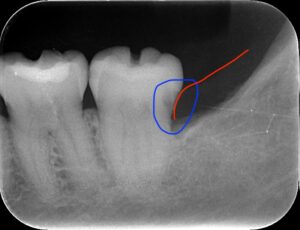

レントゲンの青い部分が虫歯です。赤い部分が

歯茎ですので歯肉縁下カリエスになります。